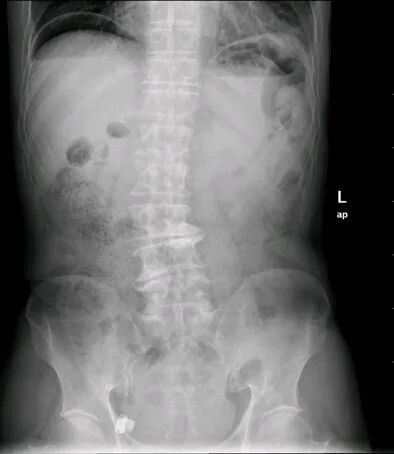

气腹

腹腔内存在游离气体的现象。多由胃肠道穿孔等所致,表现为腹部叩诊肝浊音区消失,病人站立作X线检查时,可见膈下有游离气体,如因消化性溃疡或伤寒等并发急性胃或肠穿孔时,须立即手术治疗。因诊断和治疗上需要将气体注入腹腔内所致的气腹,称人工气腹。